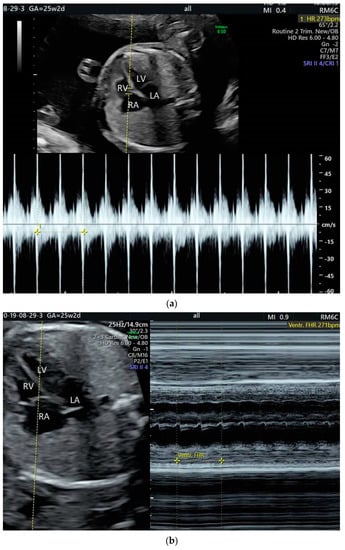

2. The Use of Ultrasound to Assess Fetal Heart Rhythm

4.2. Supraventricular Tachyarrhythmia

5.4. Heart Block